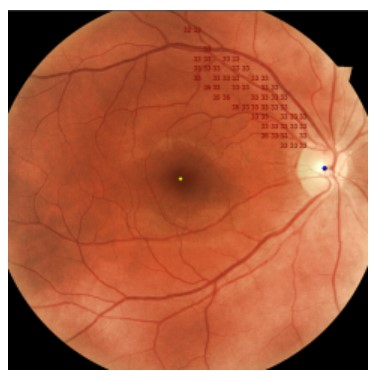

Badanie skojarzone z obrazem dna oka

Unikalna strategia Targeted Perimetry umożliwia wczytanie wykonanego wcześniej obrazu dna oka i zaznaczenie na nim obszaru wymagającego zbadania. Następnie badanie perymetryczne wykonane zostanie dla tak wyznaczonego obszaru.

Technologia ta pozwala na szybsze i bardziej dokładne zbadanie obszaru będącego przedmiotem zainteresowania.